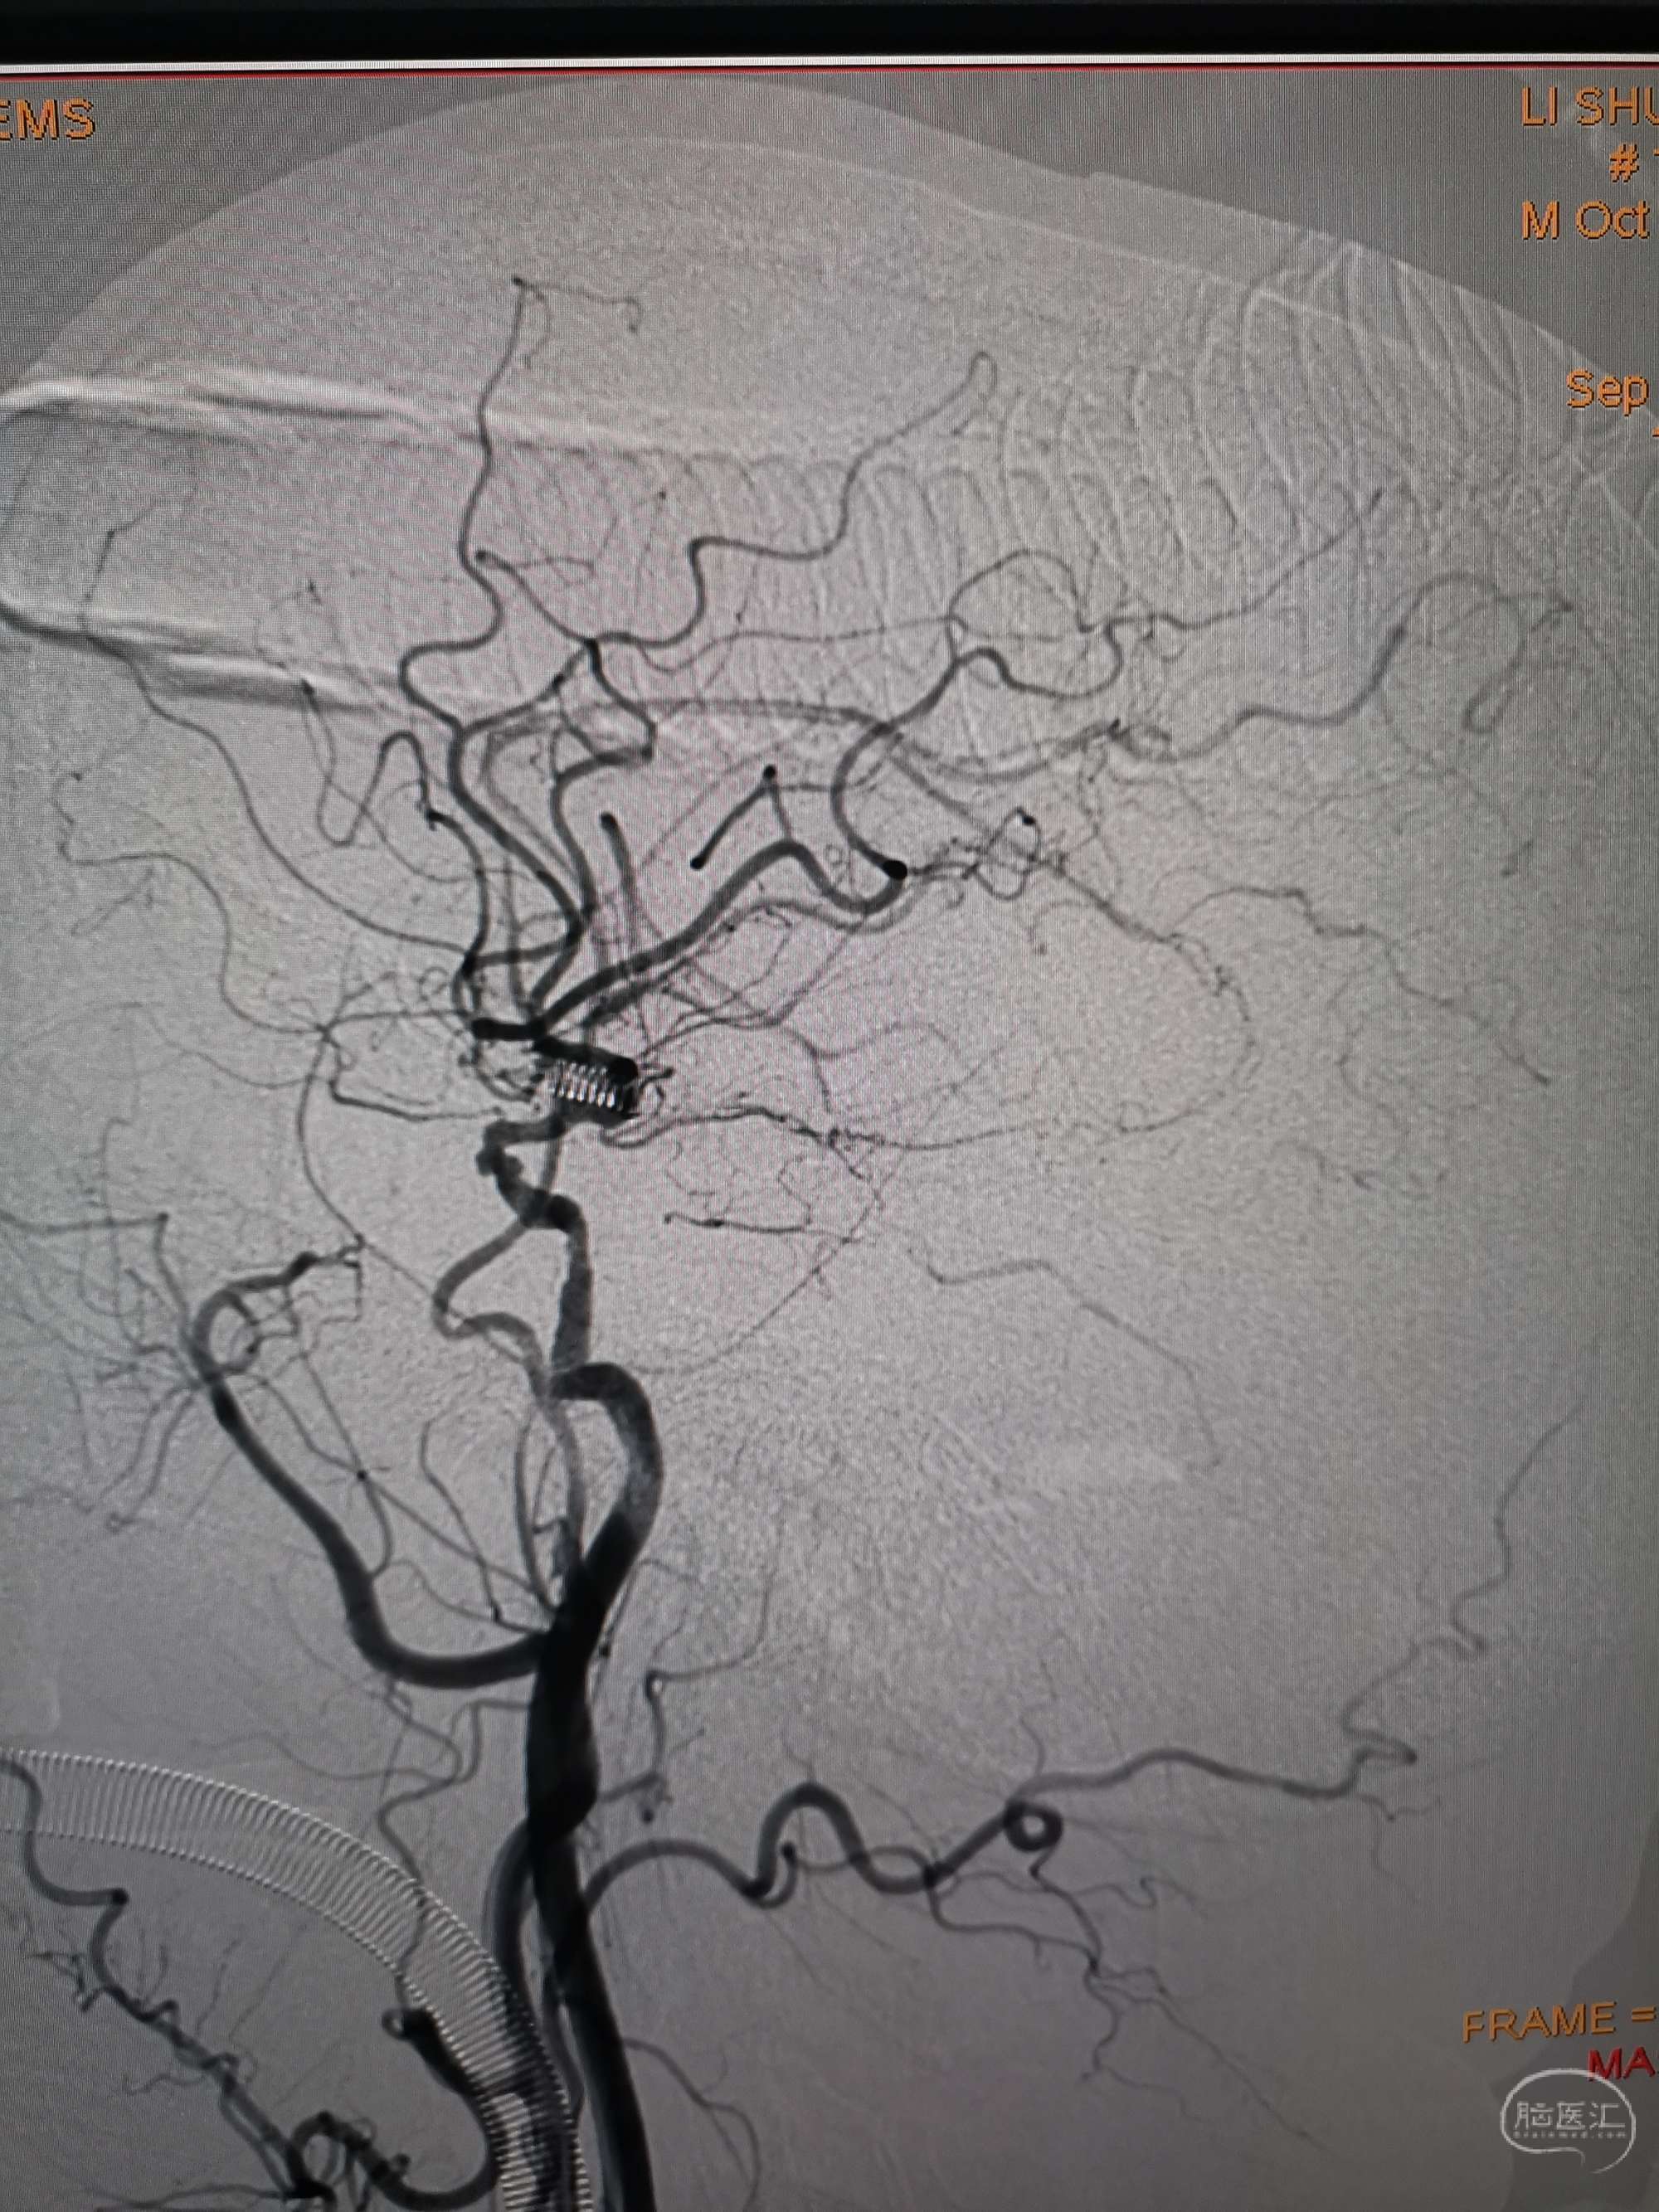

手术过程

在微导管支撑下先将微导丝和微导管穿过闭塞段,微导管超选造影证实位于基底动脉真腔后更换300cm外周交换导丝,撤出微导管后按从小到大,从远到近的原则行球囊扩张,本例手术选择了1.5✖️15、2.0✖️20、2.5✖️20球囊进行扩张,扩张满意后植入Enterprise支架,手术结束。

术后造影见左侧椎动脉闭塞段管腔恢复正常直径,远端血运良好。